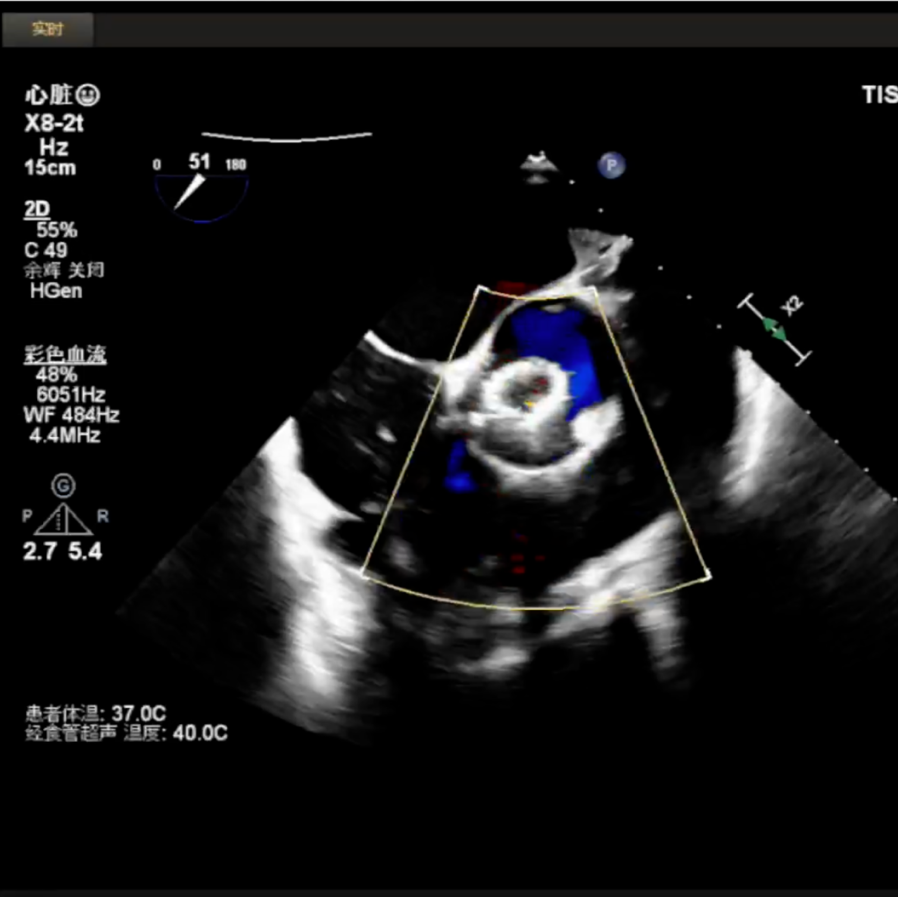

释放中期,快速起搏下释放到80%切换视图,并借助食管心超评估深度和反流情况:

超声复查,支架形态满意,手术结束: